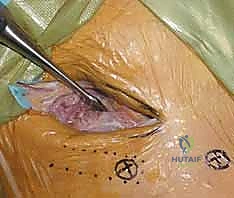

الخطوة الثالثة: إدخال المسامير المعدنية (Schanz Pins)

يتم عمل شقوق جلدية صغيرة جداً (حوالي 1-2 سم). من خلال هذه الشقوق، وبدقة متناهية لتجنب الأعصاب والأوعية الدموية، يتم إدخال مسامير معدنية سميكة ومصنوعة من التيتانيوم أو الفولاذ المقاوم للصدأ في عظام الحوض.